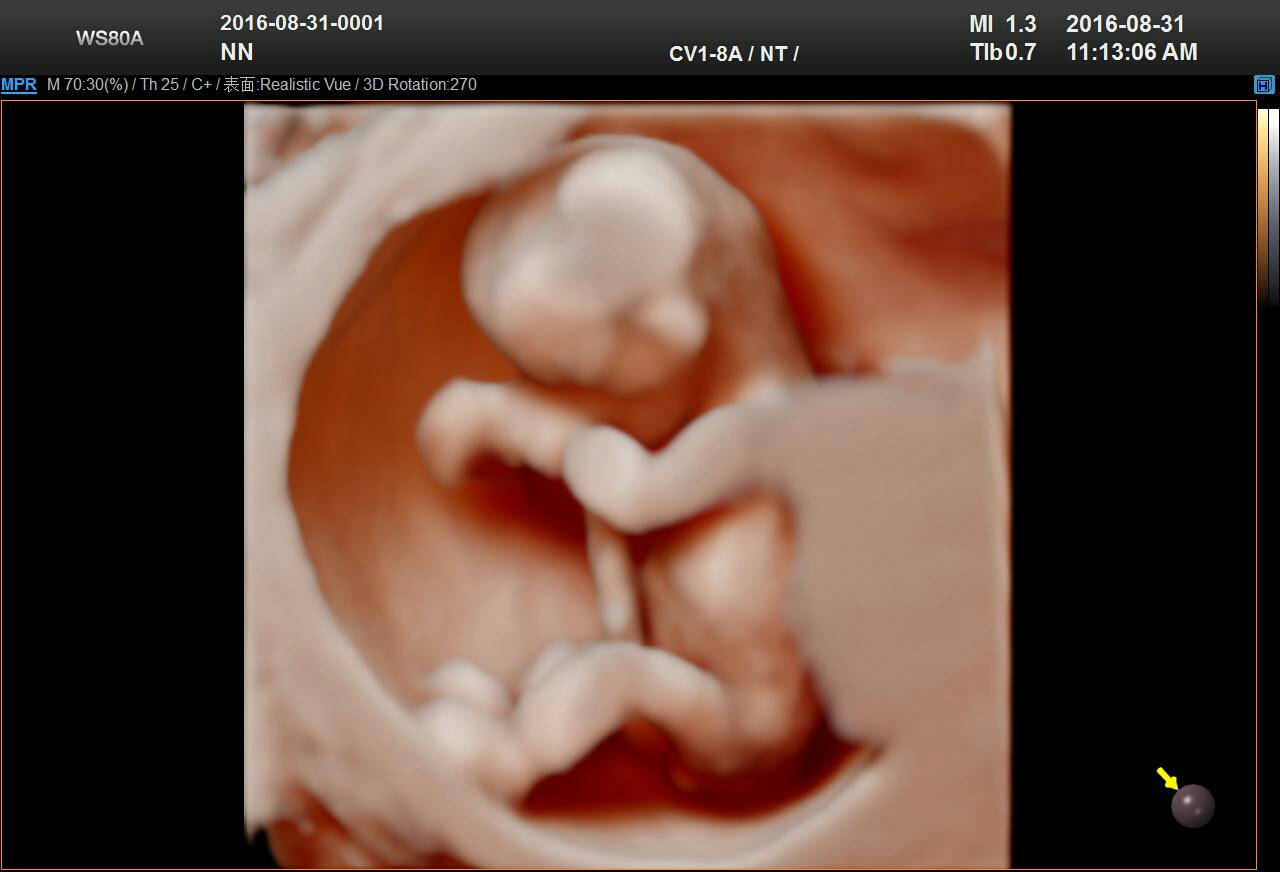

NT检查,11~13周,NT检查是孕期检查项目之一,但是不少准妈妈对于NT检查这个项目并不是十分了解。实际上,NT检查又称为颈后透明带扫描,是评估胎儿是否患有唐氏综合症的一种方法》》在线预约NT检查享优惠

四维、五维彩超是指能够显示人体内脏器官的实时活动图像,并实时获取三维图像的彩色超声设备。它是目前世界上比较先进的超声检测设备,它在原来的3D影像基础上,添加上了时间维度,能够帮助孕妇实时观察腹中胎儿的发育状况。